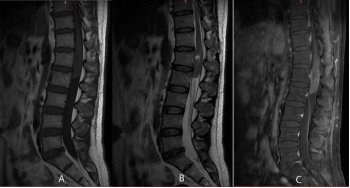

2)硬脊膜内髓外肿瘤

是指位于脊髓外部、硬脊膜下方的肿瘤,就像电缆中金属导体与绝缘层之间的部分。脊神经肿瘤和脊膜瘤(图6、7)较为常见。它们的发展过程通常比较缓慢,在早期可能会引起根性疼痛,咳嗽或打喷嚏时症状可能加重。有时还可能出现脊髓半切综合征,表现为同侧肢体无力以及对侧肢体感觉减退。

图6.L1-2水平髓外硬膜下神经鞘瘤MRI图像

图7.胸椎髓外硬膜下脊膜瘤MRI图像